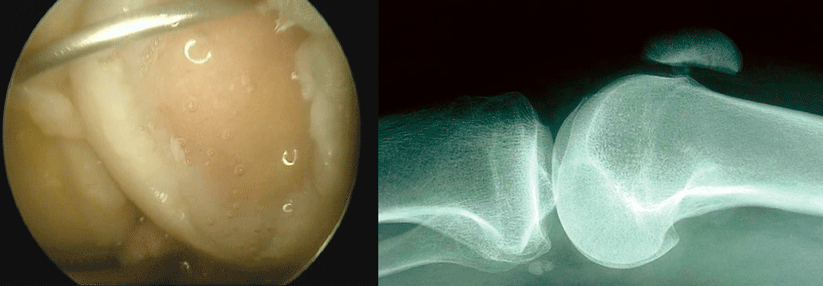

Wichtige Landmarken weisen bei der Diagnostik den Weg. Wichtige Landmarken weisen bei der Diagnostik den Weg. © Schulze et al. Wehrmedizinische Monatsschrift 2018; 62: 60-64 © Beta Verlag & Marketinggesellschaft mbH, Bonn

Ansicht lateral: 1. Tractus iliotibialis, 2. lateraler Gelenkspalt, 3. Fibulaköpfchen, 4. M. Popliteus Ansicht lateral: 1. Tractus iliotibialis, 2. lateraler Gelenkspalt, 3. Fibulaköpfchen, 4. M. Popliteus © Schulze et al. Wehrmedizinische Monatsschrift 2018; 62: 60-64 © Beta Verlag & Marketinggesellschaft mbH, Bonn

Ansicht medial: 1. medialer Gelenkspalt

2. Verlauf Pes anserinus Ansicht medial: 1. medialer Gelenkspalt 2. Verlauf Pes anserinus © Schulze et al. Wehrmedizinische Monatsschrift 2018; 62: 60-64 © Beta Verlag & Marketinggesellschaft mbH, Bonn

Ansicht frontal: 1. proximaler Patellapol/Quadricepssehne, 2. distaler Patellapol, 3. Patellasehne,

4. Tuberositas tibiae Ansicht frontal: 1. proximaler Patellapol/Quadricepssehne, 2. distaler Patellapol, 3. Patellasehne, 4. Tuberositas tibiae © Schulze et al. Wehrmedizinische Monatsschrift 2018; 62: 60-64 © Beta Verlag & Marketinggesellschaft mbH, Bonn